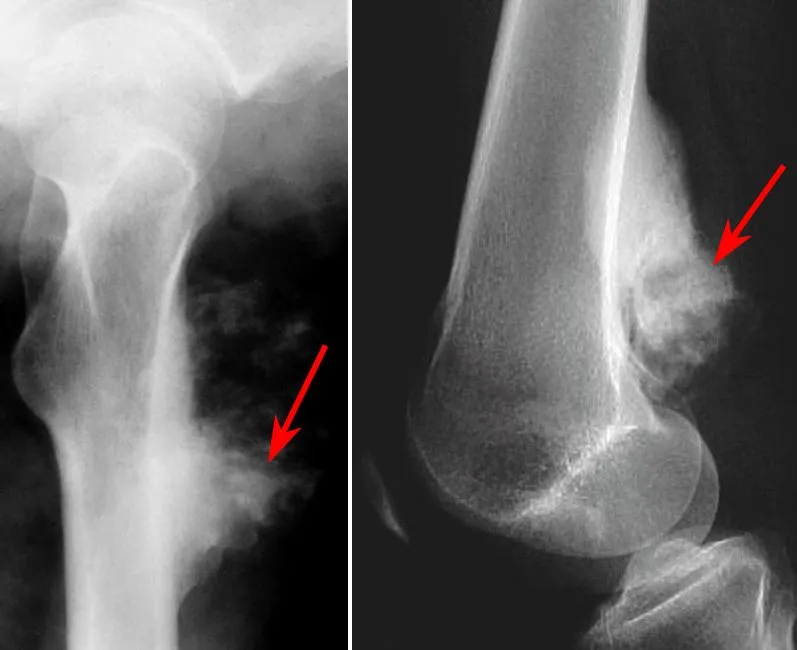

- Osteosarcoma: Most common (excl. myeloma); bone-forming.

- Sites: Metaphysis (knee, proximal humerus).

- X-ray: Sunburst, Codman's triangle.